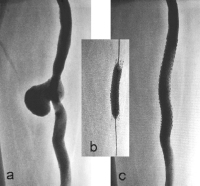

Abbildung 5a-c: (a): Angiographische Darstellung des Aneurysmas spurium nach Bypass-Ruptur; (b): Nachdilatation des gecoverten Stents mit einem Ballon 10/40 mm; (c): Abschluss-Angiographie nach Implantation eines gecoverten Stents (9/59 mm).